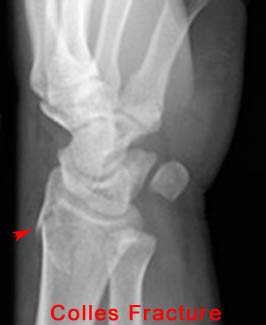

8) Name the abnormality shown in the image below.

Ulnar Styloid Process Fracture - In 50% of Colles fracture cases the ulnar styloid process is also fractured.